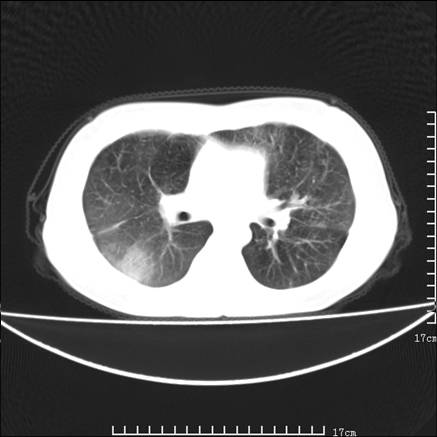

女,46岁,患胃溃疡多年,溃疡大小约1.0cm左右,后于5年前手术,病理为胃癌。主诉:半月前感冒后胸闷,气短,有咳嗽,无明显咳痰,无发热。偶有腰背部不适。

以下为高分辨扫描图像

双肺小叶间增厚,双肺散布粟米影和磨玻璃状影,以双肺上叶为重。结合病史考虑转移(癌性淋巴细管炎)可能性大。

结合病史:认为是典型肺部癌性淋巴管炎、淋巴结转移。请看图解。

肺癌性淋巴管炎征象分为主要征象及合并征象,主要征象包括:

1、近肺门支气管血管周围间质结节状增厚;

2、小叶间隔结节状增厚;

3、小叶中央间质结节状增厚;

4、胸膜下间质结节状增厚。

合并征象为:纵隔淋巴结增大,胸腔积液,肺多发随机分布的小结节等。